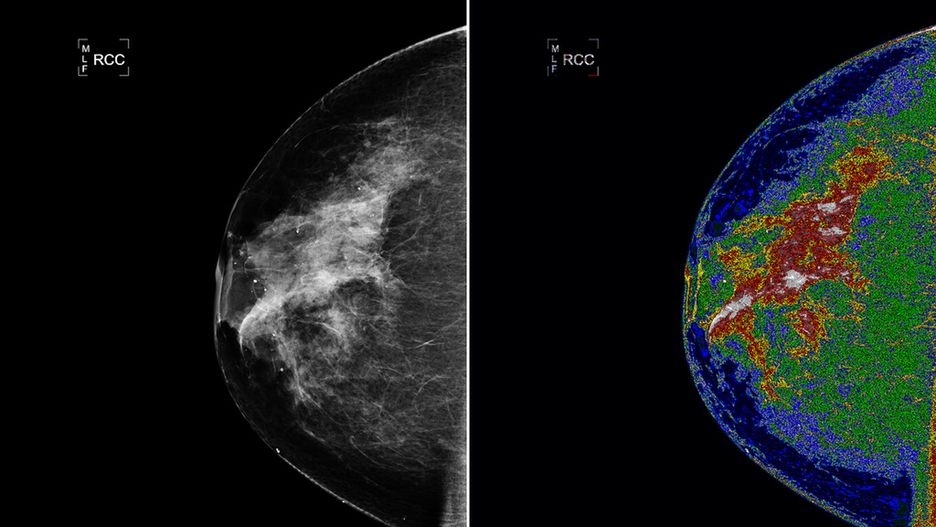

Goddard Space Flight Center w Greenbelt wspólnie z małą firmą zajmującą się tworzeniem oprogramowania medycznego - Bartron Medical Imaging, Inc. (Connecticut) - opracowały system medyczny MED-SEG. Dzięki temu lekarze otrzymają lepsze wyniki z aparatów rentgenowskich, ultrasonografów i mammografów. Pokazuje to najlepiej zdjęcie powyżej - po lewej widzimy zwykłe zdjęcie, po prawej - zdjęcie z użyciem nowego systemu. Jak powiedział dr Thomas Rutherford, dyrektor Wydziału Ginekologii Onkologicznej na Yale University:

System powstał na bazie wspomnianego programu Earth Science Imagery. Może on być używany także przez radiologów, pobierać obrazy z różnych źródeł, jak m.in. skanery czy urządzenia obrazowania medycznego, i udostępniać je w sieciach medycznych. MED-SEG pozwoli szpitalom także wysyłać obrazy przez bezpieczne łącze internetowe do centrum obróbki obrazu prowadzonego przez firmę Bartron. Tam będzie można dokonać jego przekształcenia za pomocą zaawansowanych funkcjonalności algorytmu HSEG.

Po takiej obróbce obraz zostanie wysłany z powrotem do szpitala, w którym eksperci postawią diagnozę. Bartron zainstalował już system w the University of Connecticut Health Center, a jego testy mają się odbyć jednocześnie w trzech placówkach: New York University Medical Center, Yale-New Haven Medical Center i the University of Maryland Medical Center.